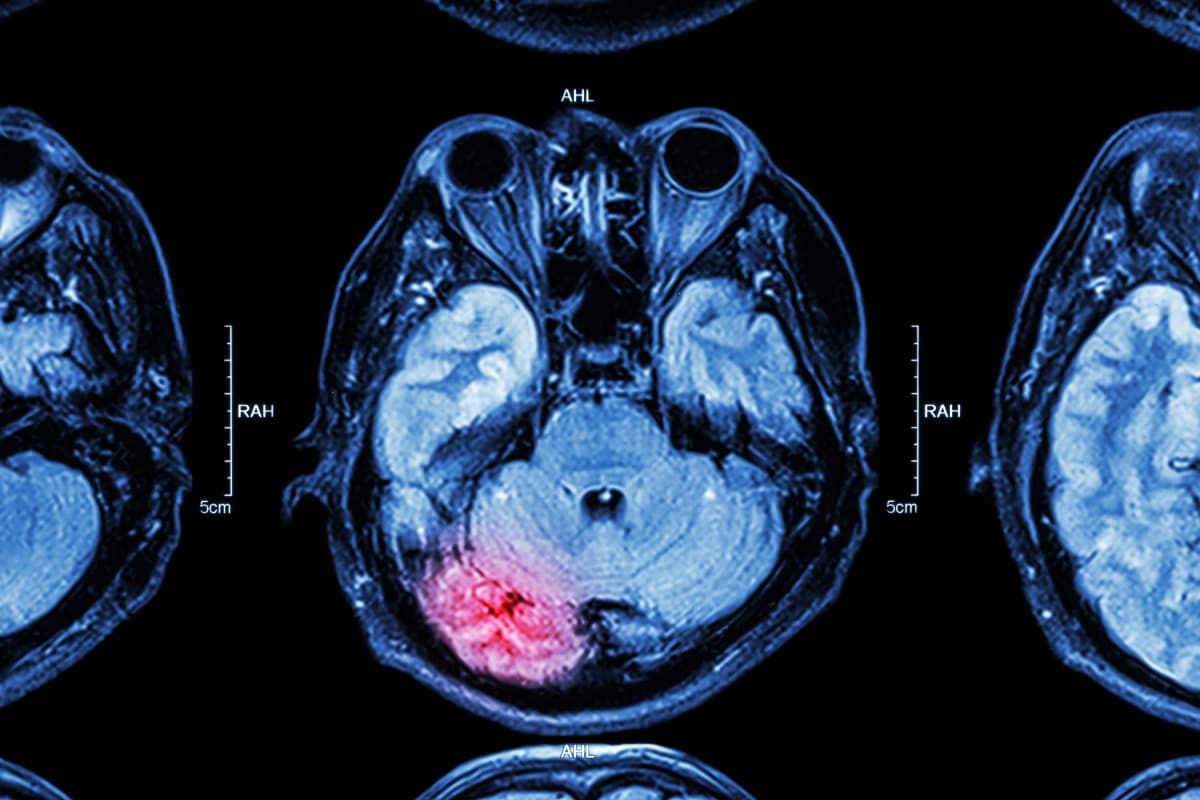

• Contusions: This injury can happen during an open head wound or a closed head wound. This type of injury causes the brain to bruise and blood to leak inside of the head when blood vessels are damaged. There can also be blood clots or fractures.

Open head wounds

Unlike closed head wounds, an open head wound happens when the skull is cracked, broken, or penetrated in any way. These injuries can happen in any number of ways and can cause swelling in the brain. It can lead to sepsis and infection. Any head wound is life-altering and should be treated properly. These injuries require a lifetime of care which is why you will need an Olathe traumatic brain injury attorney fighting to obtain compensation on your behalf.